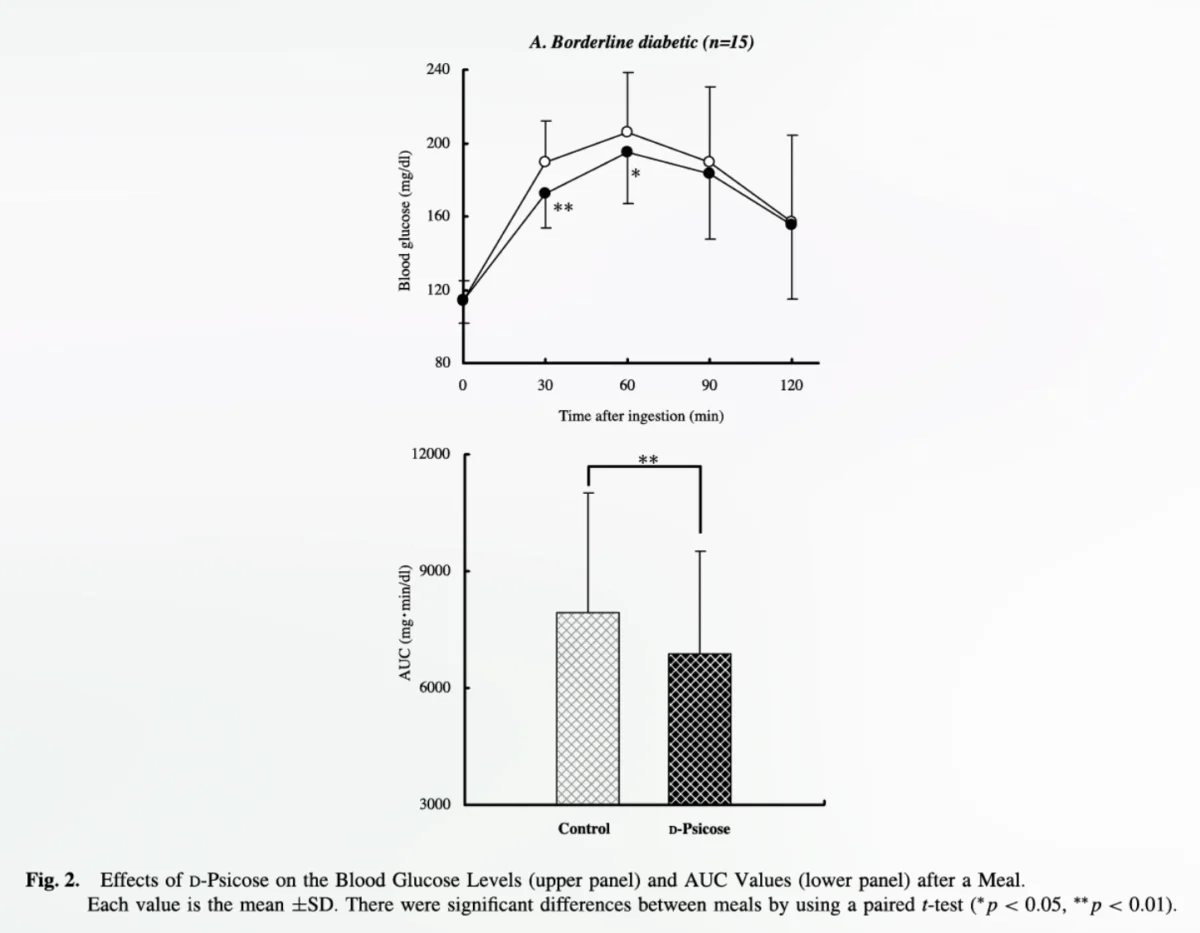

Onions: Unpacking the Evidence from Randomized Human Trials for Health Benefits

Onions, a staple in kitchens worldwide and a cornerstone of countless culinary traditions, have long been lauded for their potential health-promoting properties. While anecdotal evidence and traditional medicine have often…